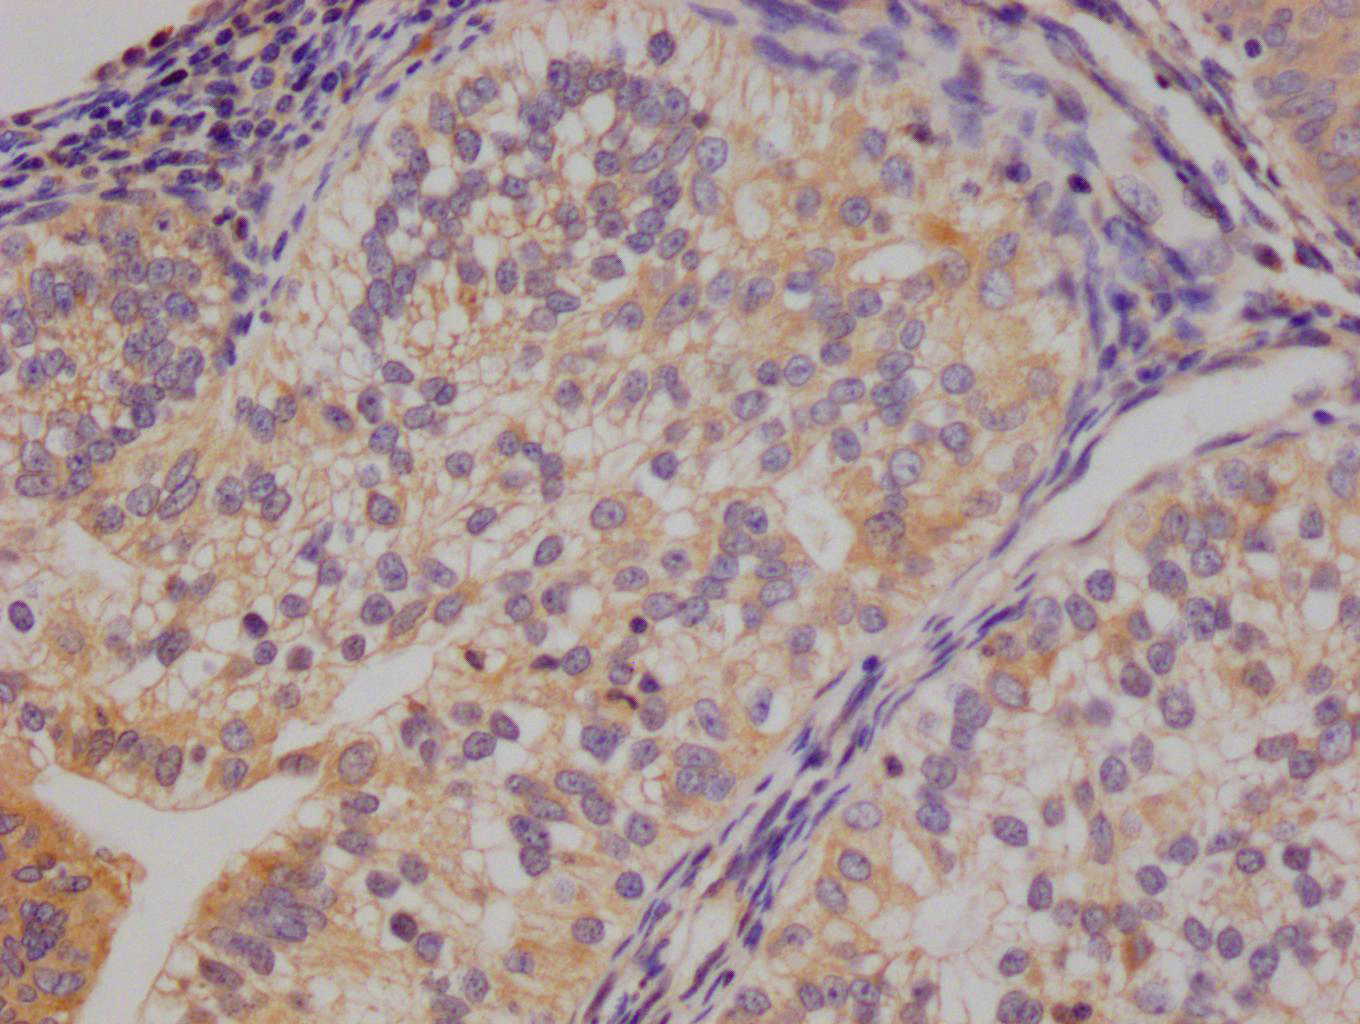

Immunohistochemistry of paraffin-embedded human lung tissue using CSB-PA001572EA01HU at dilution of 1:100